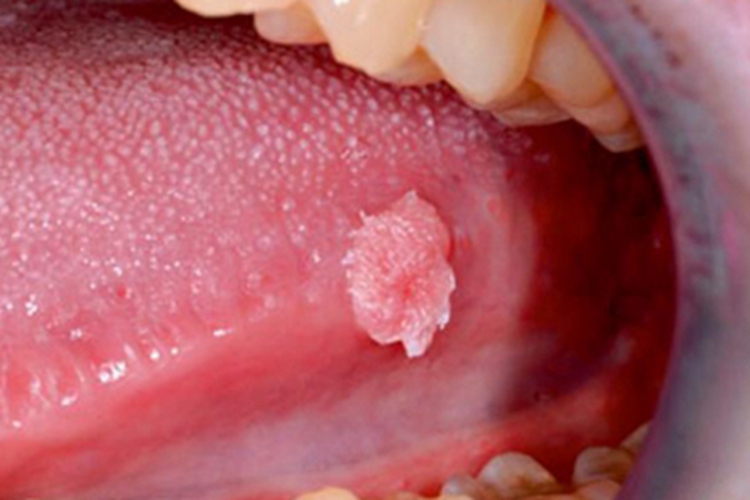

尖锐湿疣

尖锐湿疣的舌部皮损初起为单个或多个散在的淡红色小丘疹,质地柔软,顶端尖锐,随后丘疹疙瘩会逐渐增多增大,形态可呈乳头状、菜花状等,外观像长了息肉一样。但疣体表面易发生糜烂,还可合并出血及感染。多数患者无明显自觉症状,也可有异物感或疼痛不适感。